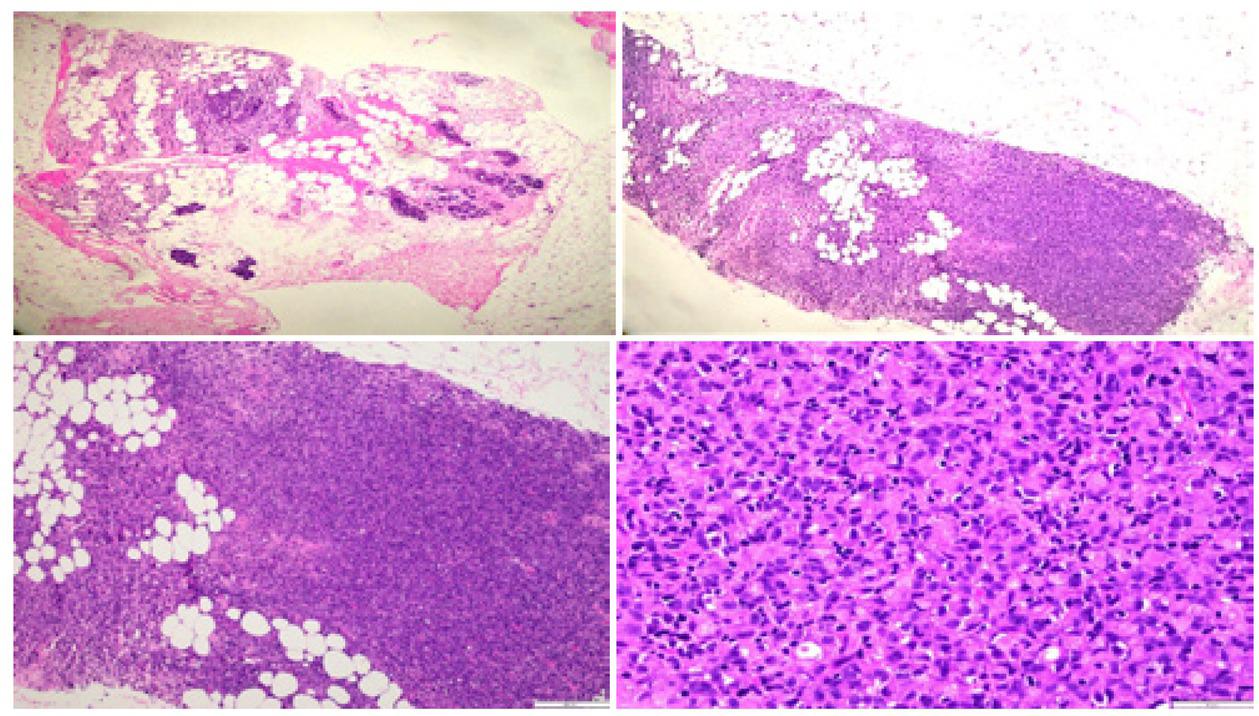

Fig. 4

Pathological examination revealed multifocal nodular aggregates of high grade tumor cells with pleomorphic nuclei and prominent nucleoli. Typical single file pattern and targetoid growth are seen infiltrating around ducts and between fat lobules. Pathological examination confirmed invasive pleomorphic lobular carcinoma